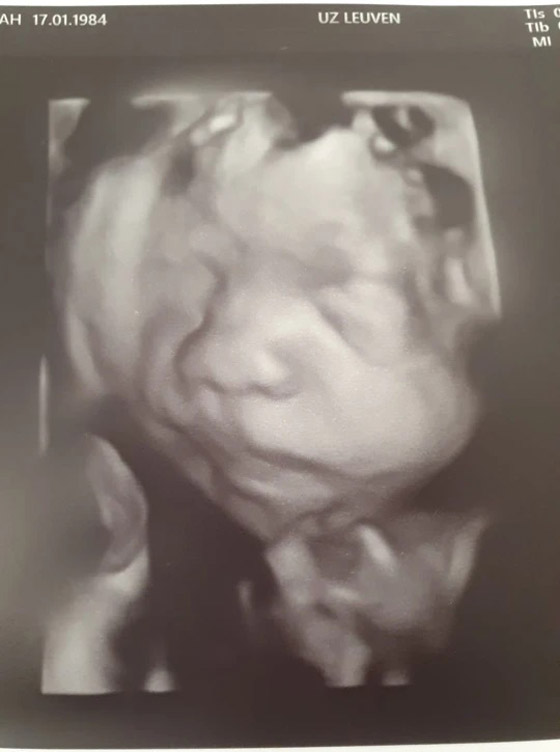

وفي سبتمبر (أيلول) 2020، سافر الزوجان ديبوا وديفيد إلى بلجيكا لإجراء العملية في حرم UZ Leuven Gasthuisberg الجامعي. جاء ذلك بعد أسابيع من الاختبارات والفحوصات للتأكد من استيفاء الطفل بريستون للمعايير، والتي تضمنت التحقق مرتين من أنه ليس لديه أي مشاكل طبية خطيرة أخرى وأن الآفة الموجودة على ظهره في مكان مناسب للعملية. وفي يوم الجراحة، تم تحذير الأم من وجود خطر كبير من خضوعها للولادة المبكرة على طاولة العمليات. وخلال العملية التي استغرقت سبع ساعات، قطع الجراحون الرحم بنفس طريقة الولادة القيصرية. وأجروا عملية على العمود الفقري لبريستون وأغلقوا الفتحة في ظهره، قبل إعادته بأمان إلى رحم والدته.